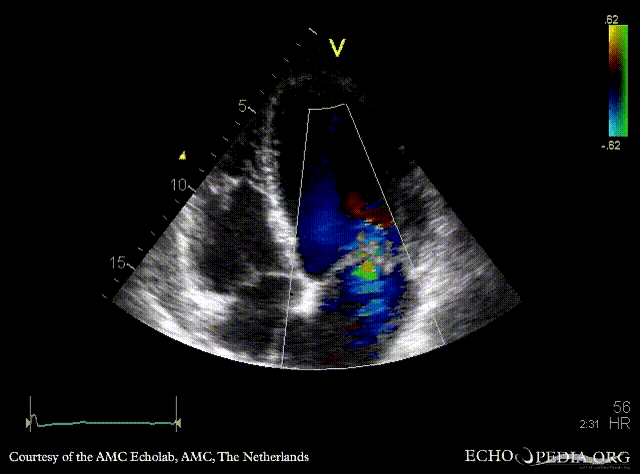

| A3CH with Color Doppler, moderate late systolic mitral regurgitation